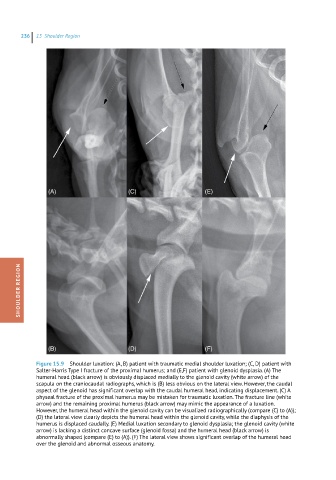

Figure 15.9 Shoulder luxation: (A, B) patient with traumatic medial shoulder luxation; (C, D) patient with

Salter-Harris Type I fracture of the proximal humerus; and (E,F) patient with glenoid dysplasia. (A) The

humeral head (black arrow) is obviously displaced medially to the glenoid cavity (white arrow) of the

scapula on the craniocaudal radiographs, which is (B) less obvious on the lateral view. However, the caudal

aspect of the glenoid has significant overlap with the caudal humeral head, indicating displacement. (C) A

physeal fracture of the proximal humerus may be mistaken for traumatic luxation. The fracture line (white

arrow) and the remaining proximal humerus (black arrow) may mimic the appearance of a luxation.

However, the humeral head within the glenoid cavity can be visualized radiographically (compare (C) to (A));

(D) the lateral view clearly depicts the humeral head within the glenoid cavity, while the diaphysis of the

humerus is displaced caudally. (E) Medial luxation secondary to glenoid dysplasia; the glenoid cavity (white

arrow) is lacking a distinct concave surface (glenoid fossa) and the humeral head (black arrow) is

abnormally shaped (compare (E) to (A)). (F) The lateral view shows significant overlap of the humeral head

over the glenoid and abnormal osseous anatomy.